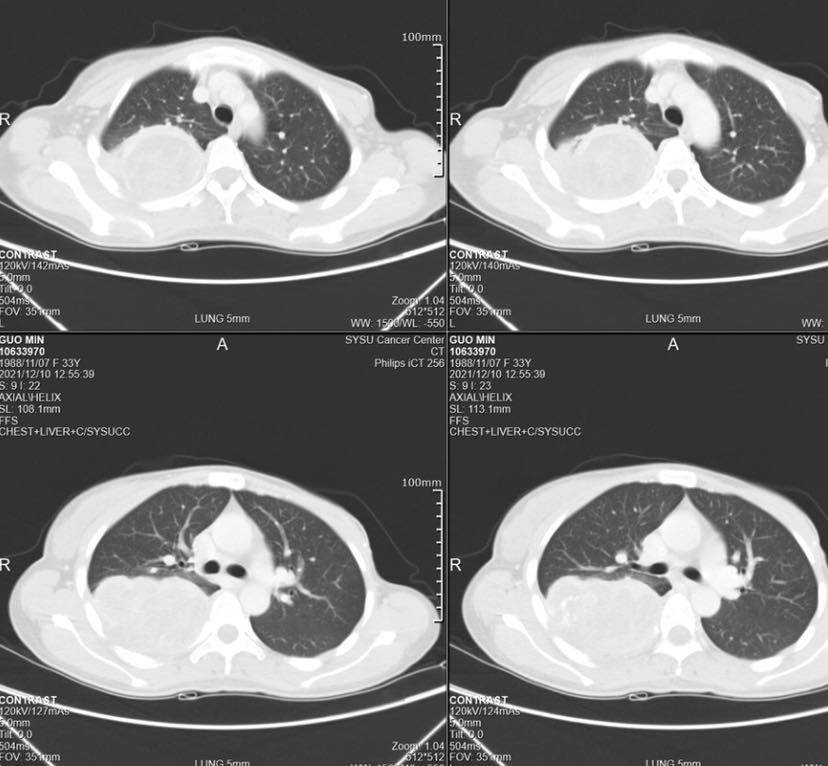

化疗两期无效后,12月10日肿瘤长的很大了,粘连胸壁也更多了

在医生的拖延下,错过了最佳手术时机,希望还有机会活下去,找办法中